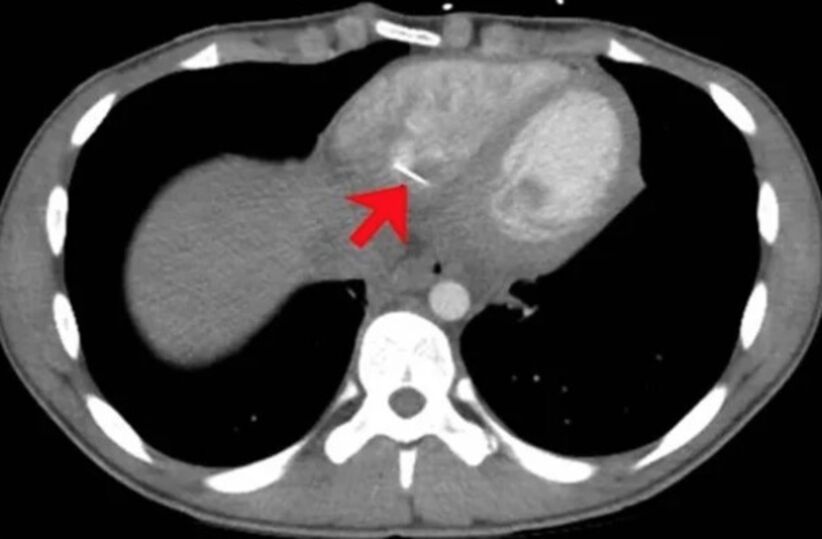

Exames de sangue também mostraram níveis altos de proteína, o que indicaria um problema no coração. Mas foi somente com uma tomografia que um “objeto linear metálico” alojado no coração foi identificado.

Se tratava do alfinete que estava no ventrículo direito do adolescente. O rapaz não lembrava de ter engolido nada, ou sofrido qualquer trauma no tórax, mas mencionou que reforma as próprias roupas e, às vezes, segura os alfinetes com a boca.